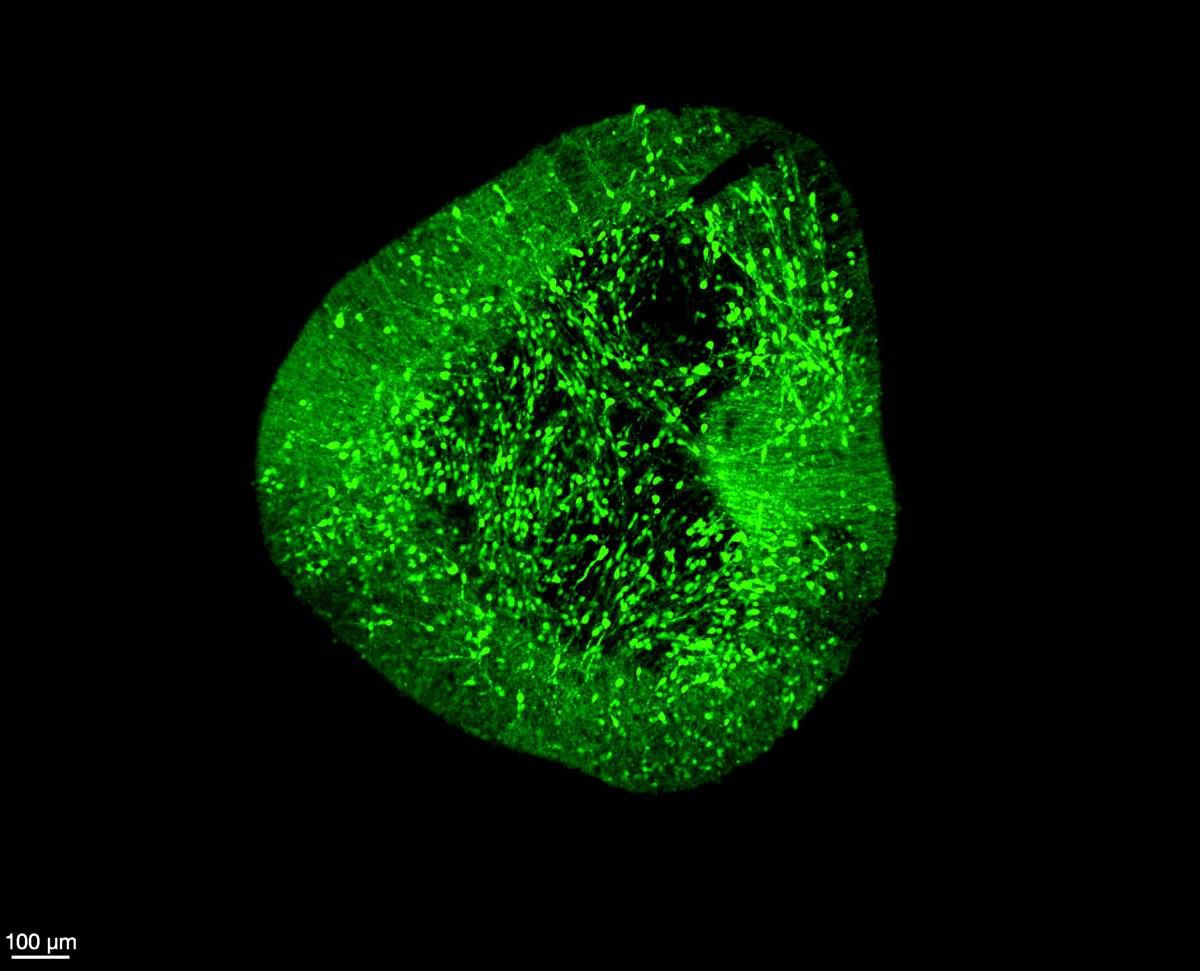

Μια ερευνητική ομάδα από το Duke-NUS Medical School παρουσίασε έναν πρωτοποριακό χάρτη του ανθρώπινου εγκεφάλου, ικανό να αποκαλύψει πώς σχηματίζονται και λειτουργούν τα νευρικά κύτταρα σε μοριακό επίπεδο. Το εγχείρημα, γνωστό ως BrainSTEM (Brain Single-cell Two tiEr Mapping), καταγράφει σχεδόν 680.000 κύτταρα του αναπτυσσόμενου ανθρώπινου εγκεφάλου και αναμένεται να ανοίξει νέους δρόμους στην κατανόηση και θεραπεία της νόσου του Parkinson.

Η μελέτη, που δημοσιεύτηκε στο περιοδικό Science Advances, δημιουργεί για πρώτη φορά έναν ολοκληρωμένο μονοκυτταρικό «άτλαντα» που χαρτογραφεί κάθε τύπο κυττάρου, το γενετικό του αποτύπωμα και τις αλληλεπιδράσεις του με τα υπόλοιπα. Με αυτόν τον τρόπο, οι επιστήμονες μπορούν να συγκρίνουν τα αποτελέσματα των εργαστηριακών μοντέλων με την πραγματική βιολογία του ανθρώπινου εγκεφάλου, κάτι που μέχρι σήμερα ήταν εξαιρετικά δύσκολο.

Η ομάδα του καθηγητή Joshua Yang στο Duke-NUS ανέπτυξε μια δισδιάστατη μέθοδο χαρτογράφησης — τη λεγόμενη προσέγγιση δύο επιπέδων — που εξετάζει πρώτα το σύνολο των κυττάρων του εμβρυϊκού εγκεφάλου και στη συνέχεια εστιάζει με ακρίβεια στον μέσο εγκέφαλο, εντοπίζοντας τους ντοπαμινεργικούς νευρώνες.